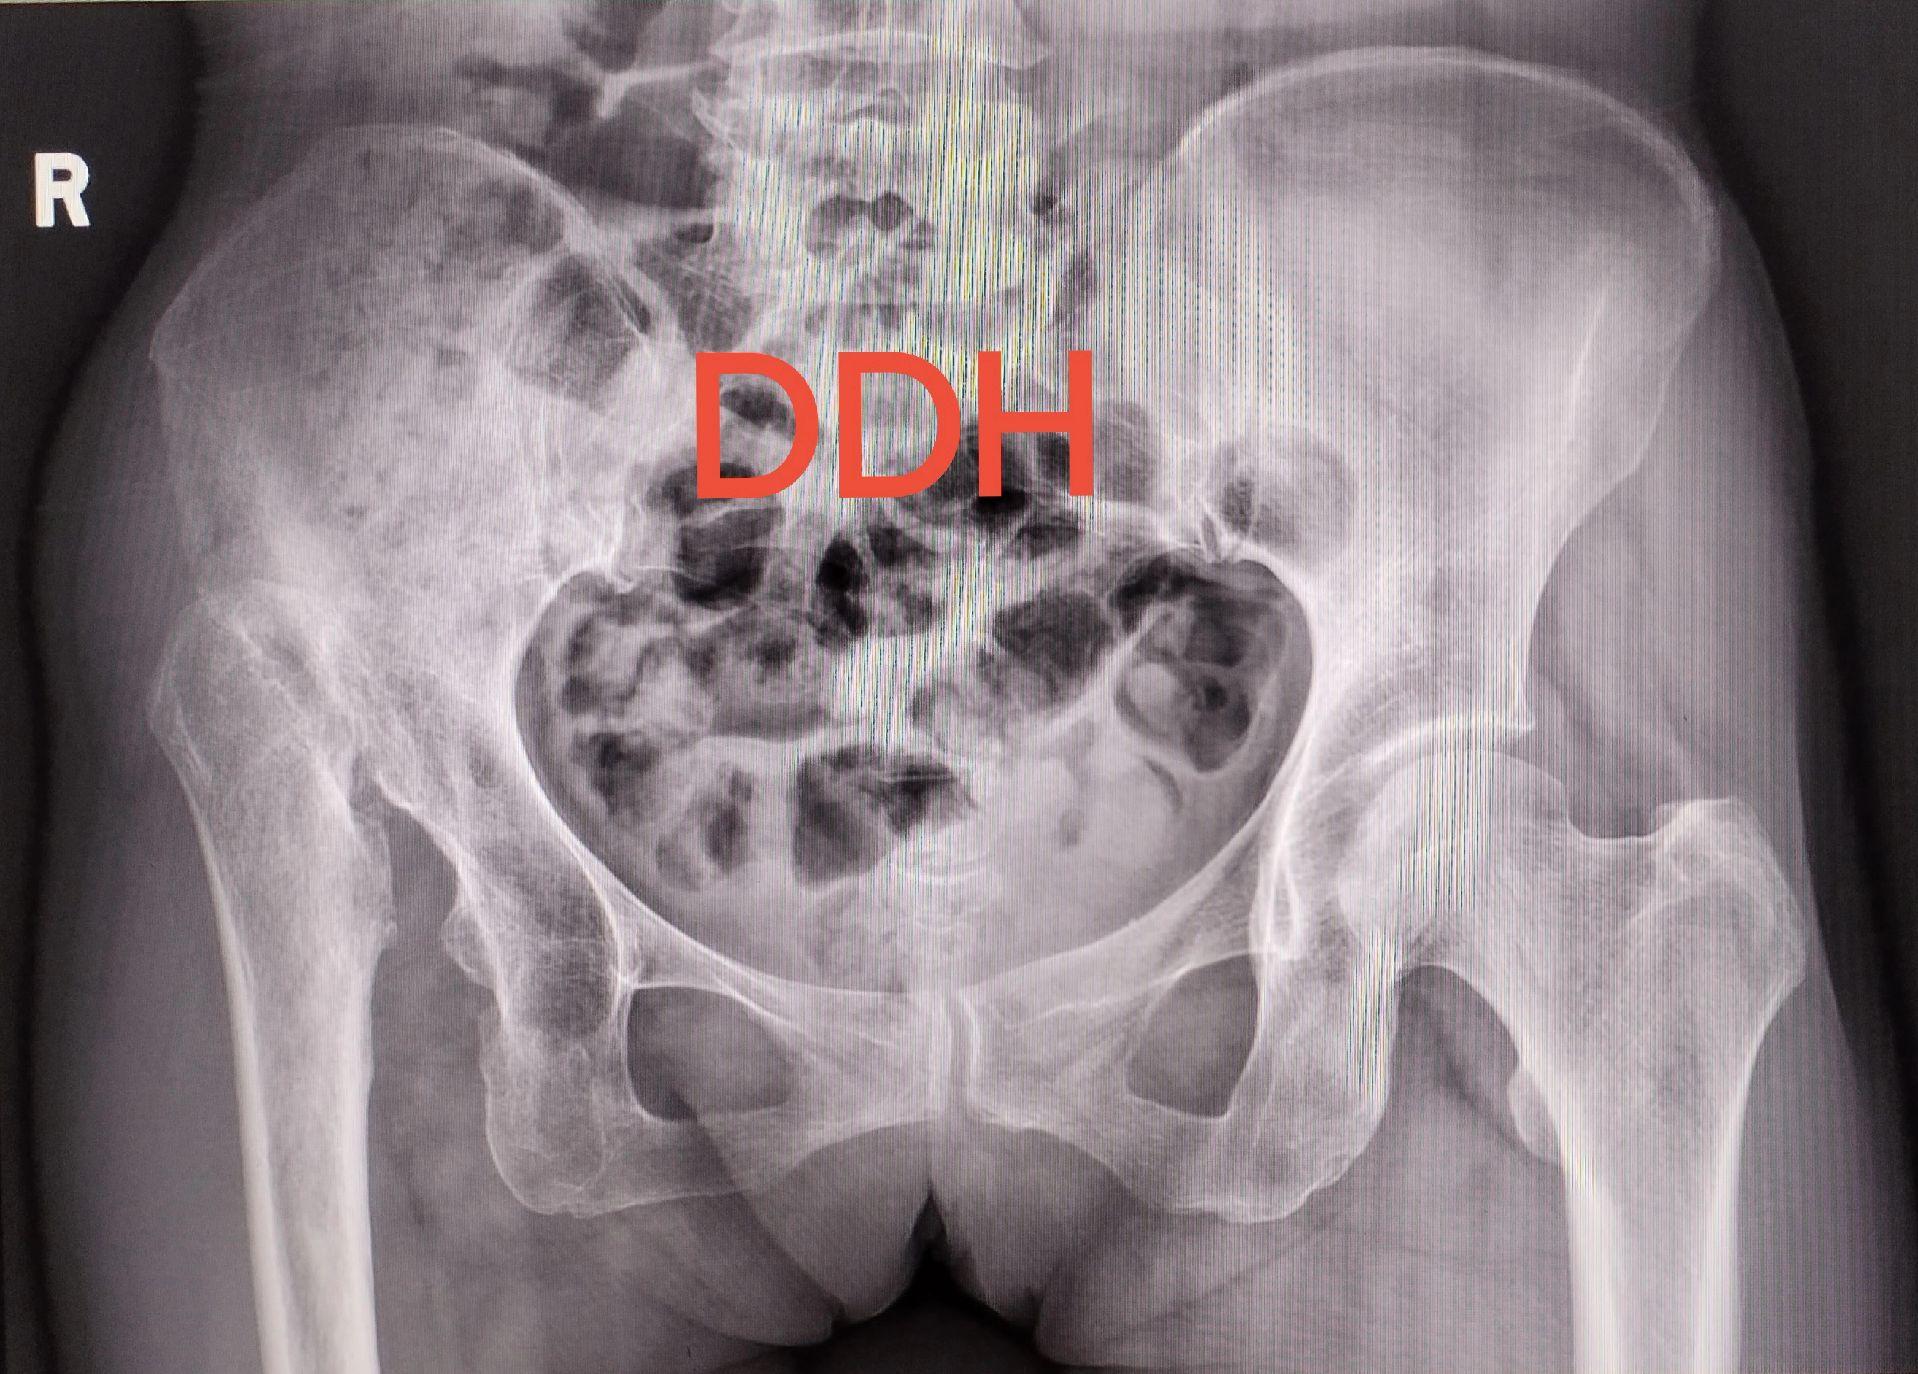

髋关节置换。DDH(先天性髋关节发育不良)四型高脱,要乐观,相信目前的技术,要有信心🌹